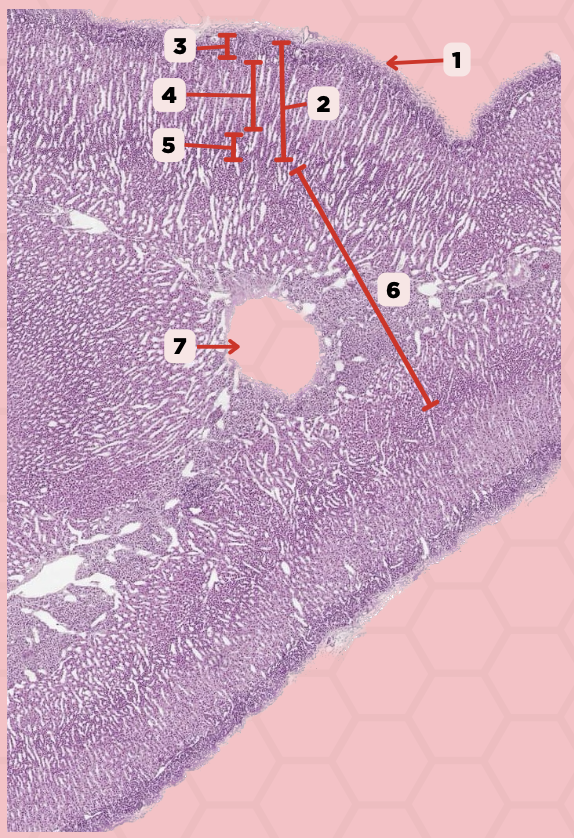

Pituitary

Identify the specimen.

Anterior Lobe

Identify the structure labeled as 1.

Posterior Lobe

Identify the structure labeled as 2.

Intermediate Lobe

Identify the structure labeled as 3.

Pars Tuberalis

Identify the structure labeled as 4.

Pituitary Stalk

Identify the structure labeled as 5.